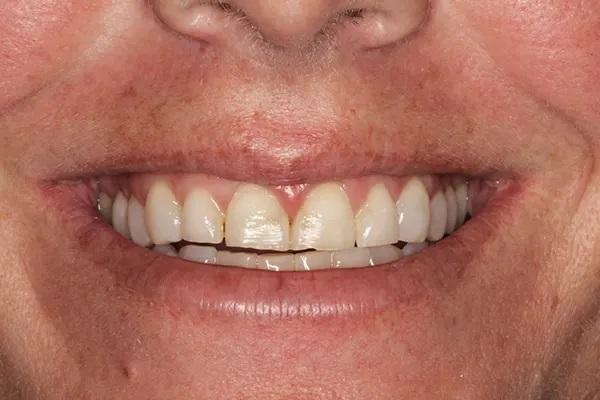

Для постоянной фиксации виниров использовался полупрозрачный цемент (RelyX Veneer Cement, 3M Oral Care) виниры были зафиксированы парами начиная с области центральных резцов, затем латеральные резцы и заканчивая клыками. Каждую реставрацию закрепляли с помощью 3-секундного светового отверждения, а излишки цемента удаляли с помощью ультразвукового скеллера. Окончательное отверждение осуществлялось путем полимерезации светом в течение дополнительных 20 секунд на каждый зуб. Результаты проведённого лечения показаны на фото с 9 по 12. Изменение улыбки пациентки с фиксированными постоянными реставрациями (фото 9). Демонстрация смыкания после лечения (фото 10). Портретная фотография анфас с широкой улыбкой (фото 11). Прицельные снимки зубов пациентки после проведенного лечения (фото 12).

Фото 9